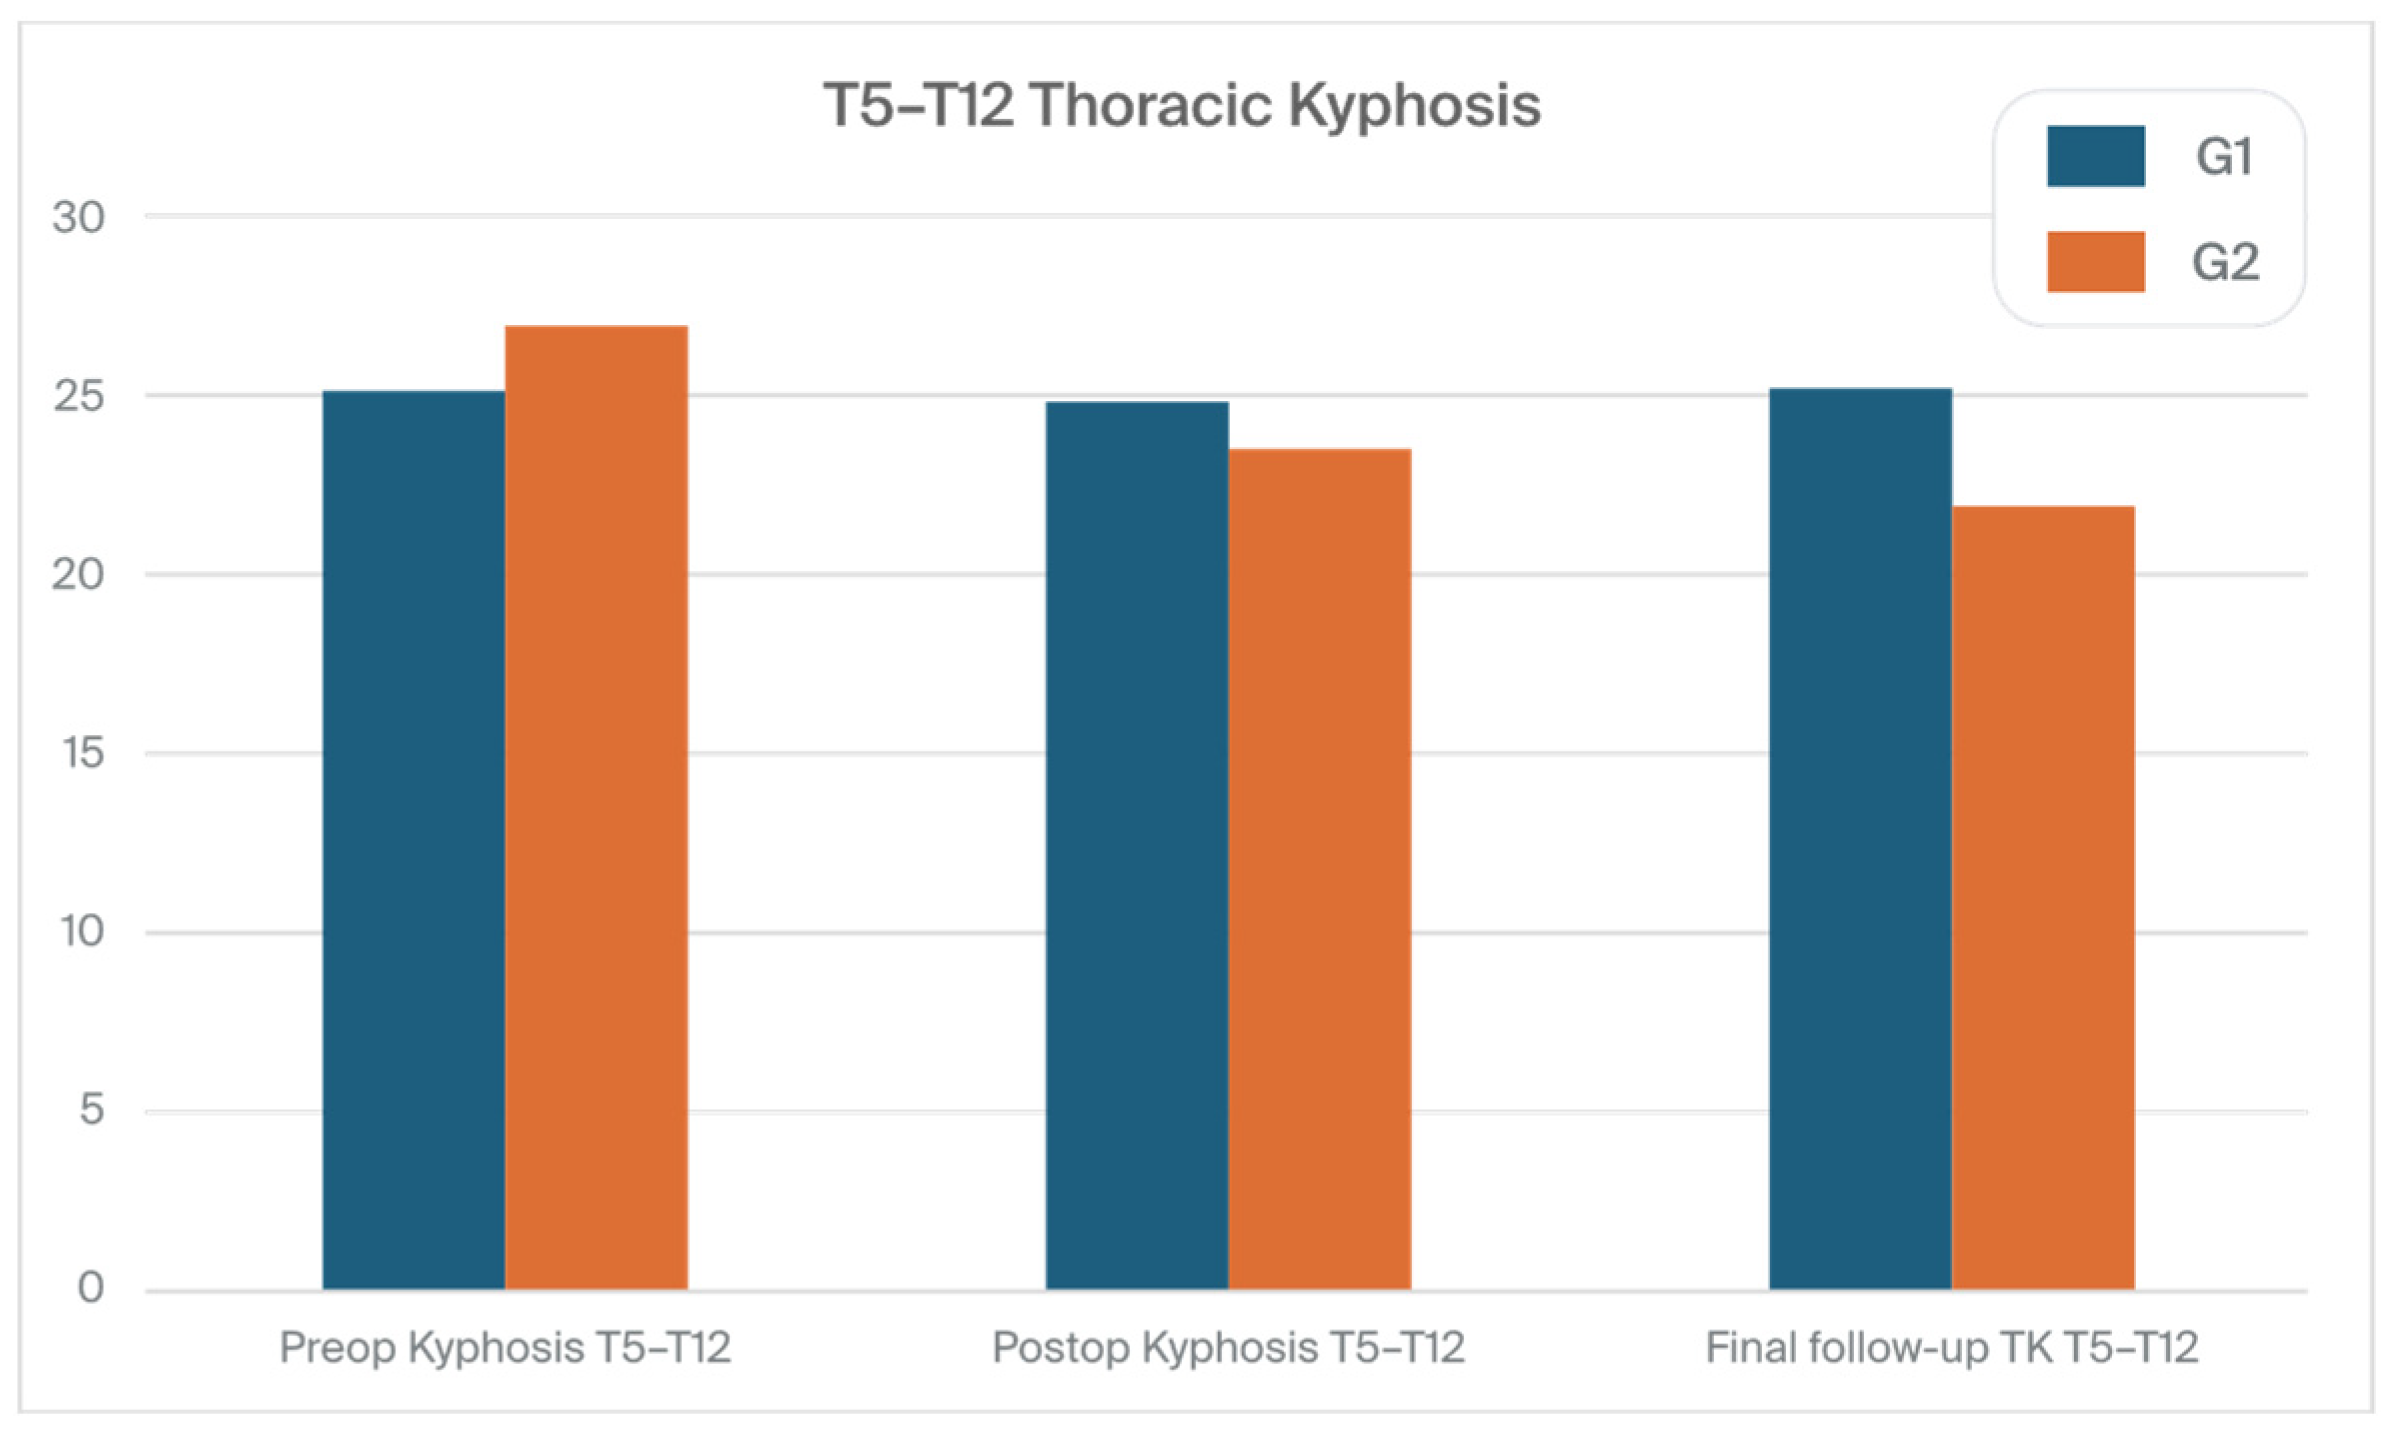

3.1. Clinical Characteristics and Radiographic Outcomes

| Preop kyphosis T5–T12 | 25.1 (15.5) | 26.9 (15.8) | 0.779 |

| Postop kyphosis T5–T12 | 24.8 (8.8) | 23.5 (10.8) | 0.012 |

| Final follow-up TK T5–T12 | 25.2 (9.8) | 21.9 (10.2) | 0.001 |